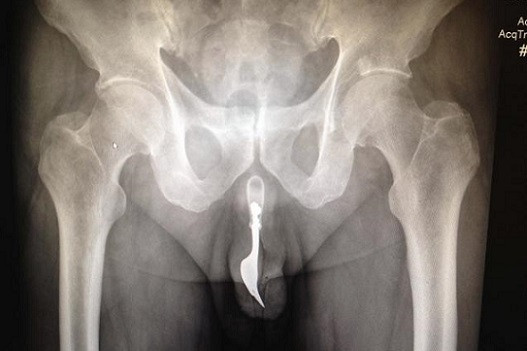

Hình ảnh chiếc dĩa nằm trong "cậu nhỏ" cụ ông

Theo một bài báo xuất bản trên tờ Tạp chí quốc tế về các trường hợp phẫu thuật, chiếc dĩa có chiều dài khoảng 10 cm đã được cụ ông tự nhét vào cơ quan niệu đạo khoảng 12 tiếng trước khi ông phải nhập viện. Nếu bằng mắt thường nhìn từ ngoài vào thì không thể thấy chiếc dĩa.